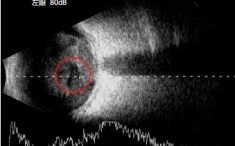

在取得老李同意后立即启动绿色通道。当天急诊为他实施左眼玻璃体切除手术,术中探查发现老李是因为外伤导致左眼隐匿性巩膜裂伤,没有得到及时治疗,引发的感染性眼内炎。历经3小时仔细操作,术中清除眼内化脓组织,注入硅油支撑视网膜,并注射万古霉素抗感染。

玻璃体切割手术中使用3D显微镜的OCT查看视网膜